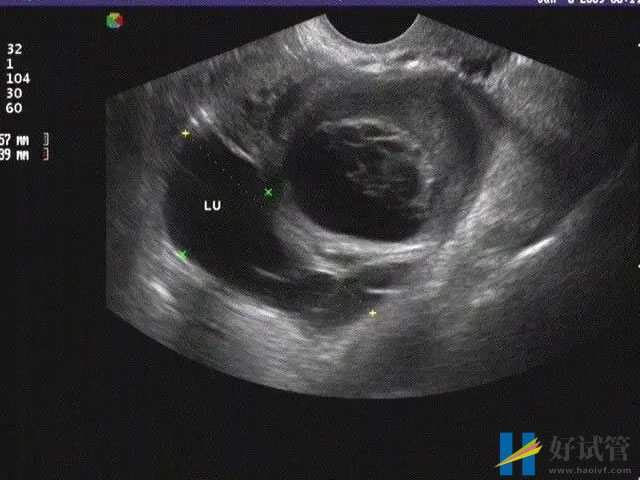

输卵管堵塞的类型

临床上面根据堵塞的严重程度可以将输卵管堵塞分为输卵管通而不畅、输卵管闭塞不通和输卵管完全不通这三种类型。不同的情况带来的病症也是不一样的,具体如下:

- 输卵管通而不畅:这个主要是因为脱落细胞、血块阻塞、邻近器官粘连等因素所导致的。对这类输卵管堵塞的治疗西医以腹腔镜疏通治疗为主;

- 输卵管闭塞不通:大概率是因为结核、附件炎、宫外孕、输卵管结扎等因素导致的,一般通过腹腔镜或宫腔镜检查可以直观的判断,可以采用西医以导丝复通术为主进行治疗;

- 输卵管完全不通:这种是比较严重的,大多数是因为没有及时治疗,或者是输卵管结核感染引起的,只能采用宫腹腔镜手术治疗,不过即使疏通成功,也很难自然受孕。